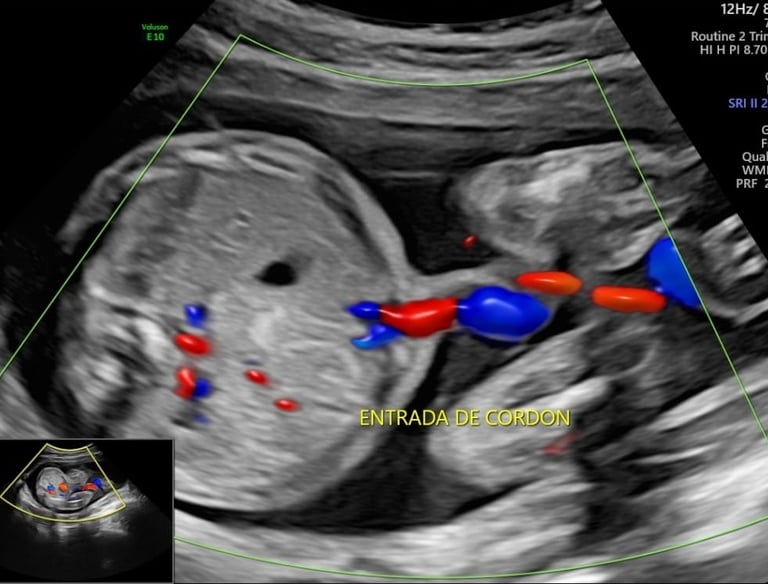

Ultrasonido Estructural

Es la revisión más importante y detallada de todo tu embarazo.

Este estudio, se realiza entre las semanas 18 y 22, es el "check-list" de salud más completo para tu bebé.

Seguimiento del crecimiento fetal, líquido amniótico, placenta y circulación materno-fetal mediante Doppler.